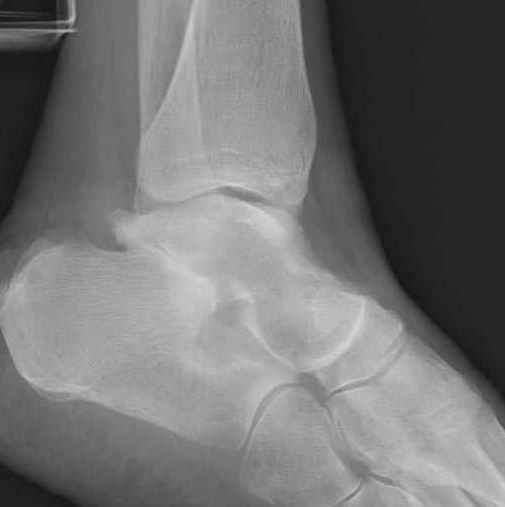

За пару недель насчитал 5 больных с переломом таранной кости, из них двое с двусторонним повреждением.

Из-за отека на стопе тактика лечения у всех была

одинаковая: временная наружная фиксация до спадения отека, при изолированных переломах они выписывались домой и через дней 7 госпитализировались на оперативное лечение.

Примеры на снимке...